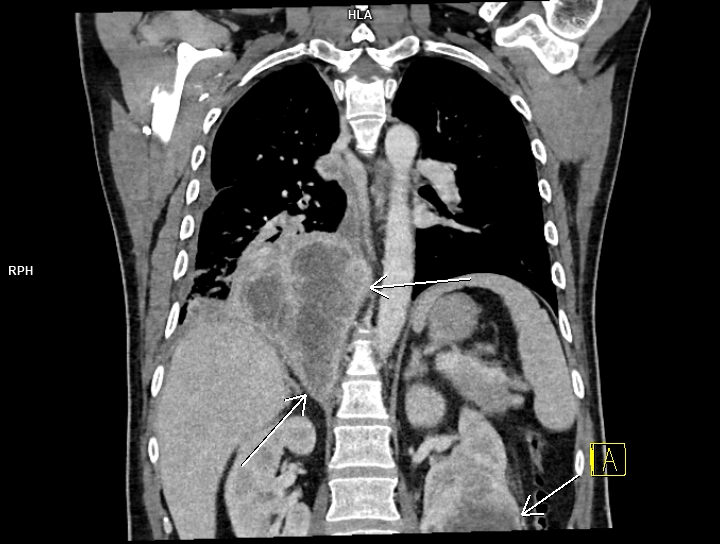

Figura 4: coronal CT în timp venos torace și abdomen

Discuţie caz nr 99: pacientul s-a prezentat în urgență și a fost trimis la examinarea CT cu suspiciune de trombembolism pulmonar. Examinarea CT efectuată toracic care a surprins și o parte din abdomenul superior evidențiază trombembolism pulmonar acut stâng la nivelul arterei intermediare cu evoluție și la nivelul arterelor segmentare și subsegmentare precum și tumoră renală stânga de pol inferior cu aspect de carcinom cu celule clare (Grawitz) și determinări secundare pleurale drepte.